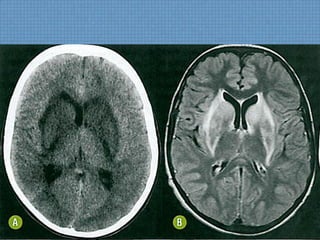

ACHADOS DE IMAGEM

• TC;

– Hipoatenuação bilateral e simétrica dos núcleos

lentiformes, com efeito expansivo relacionado ao edema e

sem impregnação;

• RM;

– Hipossinal marcante em núcleos lentiformes em T1;

– Hiperssinal em T2 em núcleos lentiformes;

SINAL DO LENTIFORME BIFURCADO

RECOMENDAÇÕES

• Diagnóstico Confiável;

– Sinais extrapiramidais pós-diálise + Hiperssinal T2/FLAIR

em lentiformes bilateralmente;

• Acidose metabólica é condição necessária para o

aparecimento do sinal do lentiforme bifurcado;

• A clínica neurológica é oriunda do edema cerebral

devido ao gradiente osmótico ureico;